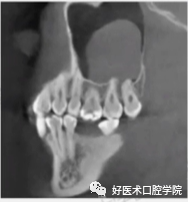

常见上颌窦底部,局部黏膜充血外渗膨胀,由于液体潴留在结缔组织而产生,呈微小的半球形或椭圆形,均匀而且不透明,CBCT和根尖周片显现明显,表现为上颌窦底的穹窿形,未被上皮包绕固称为假性囊肿,多被认为是牙源性感染导致,多可见因牙周病或根尖周病破坏的牙槽骨。